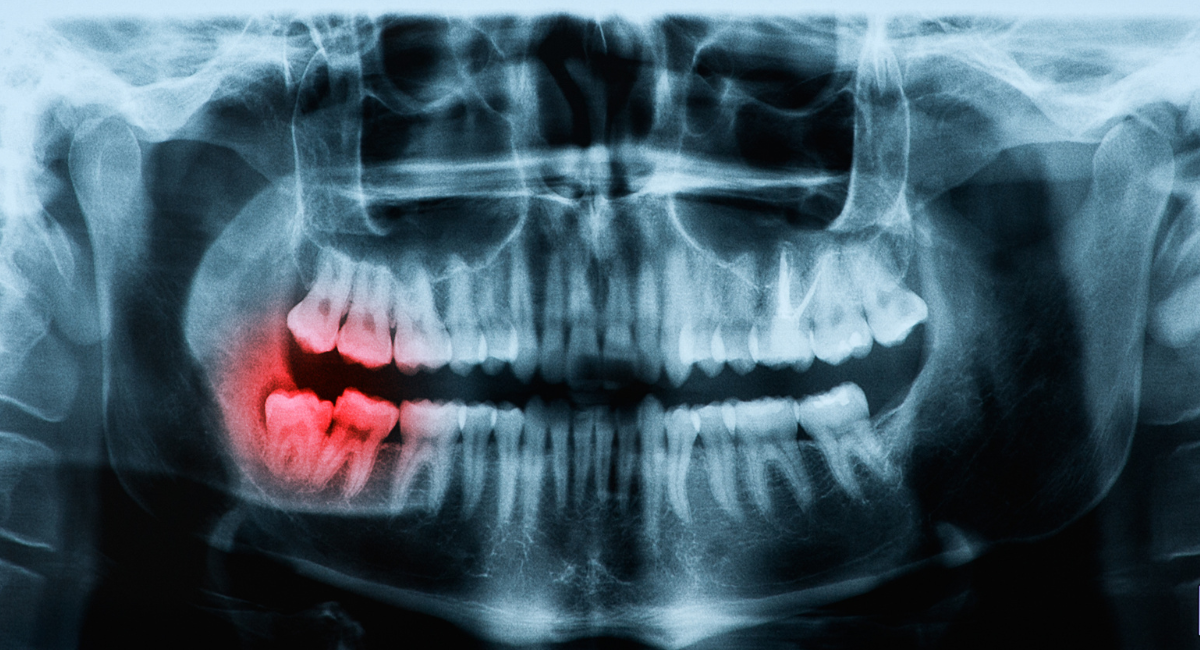

親知らずの抜歯において最も大切なのは、処置そのものよりも事前の診断です。見た目だけで「抜いたほうがよい」「今は様子を見ましょう」と判断するのではなく、歯の根の形や向き、周囲の骨や神経との位置関係まで把握することで、適切な治療方針を立てることができます。

特に下顎の親知らずは、下歯槽神経という重要な神経の近くに位置していることがあり、診断を誤ると術後のしびれなどのリスクにつながる可能性があります。そのため、レントゲンや必要に応じた精密検査を行い、リスクを想定した上で治療計画を立てることが不可欠です。

歯ぐきの中に歯が埋まっており、70~80%は骨に埋まっている状態です。「水平埋伏智歯」と呼ばれます。注意事項

術前にCT撮影を行います。処置時間は30分程度です。麻酔後に切開し、歯を割って抜歯したら2~3針縫合します。術後3日程度は腫れるかもしれませんので、鎮痛剤・抗生物質を服用してください。 -

完全に骨に埋まった親知らず

難易度 ★★★★

状態

親知らずが骨の中に埋まっている状態です。慢性的に排膿(はいのう)しています。注意事項

術前にCT撮影を行います。処置時間は45分程度です。麻酔後に切開し、神経の損傷を避けて抜歯したら2~3針縫合します。同時に歯周病の治療も行います。術後は腫れますので、鎮痛剤、抗生物質を3~5日服用してください。 -

完全に骨に埋まり歯根が神経に近い親知らず

難易度 ★★★★★

親知らずが顎の骨の中に埋まり、膿の袋を形成している状態です。神経と歯根が絡みあっています。注意事項

処置時間は左右合わせて60~90分です。入院し、全身麻酔を施したうえで手術を行います。左右を抜歯し、のう胞の摘出をします。神経麻痺が生じる可能性があるので注意が必要です。

レントゲン・CTを用いた正確な診断

親知らずは、見た目だけでは判断できない要素が多い歯です。歯ぐきの中や骨の中に埋まっている場合も多く、歯の向きや根の形、周囲組織との関係性は、外からは分かりません。そのため横浜市鶴ヶ峰駅の歯医者・歯科、横浜グランアズーリデンタルクリニック鶴ヶ峰では、通常のレントゲン検査に加え、必要に応じてCT撮影を行い、立体的な情報をもとに診断を行います。